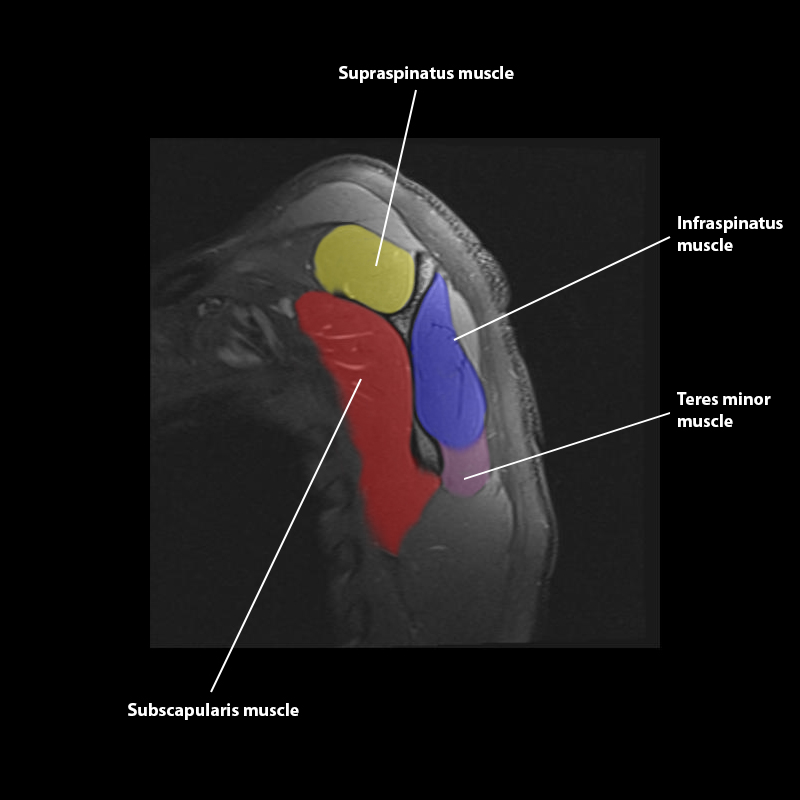

Shoulder MRI Anatomy